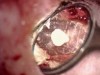

The adoption of the DOM has enabled a well-trained practitioner to treat teeth successfully that in the past might have been considered hopeless.3 These include, but are not limited to, teeth with root and/or furcation perforations, extremely calcified canals, separated instruments in the canals, and failing endodontic treatment. The microscope has also changed the unpredictable nature of apicoectomy procedures and properly addresses intricate root end anatomy (Figure 3 and Figure 4) to ensure success (Figure 5 and Figure 6).2 All in all, the DOM has fundamentally changed the clinical practice of endodontics, and all U.S. endodontic postgraduate programs now require training in microscopic endodontic techniques.4

Fig 3. Class I retro-preparation parallel to the long axis of the root as seen through the DOM with the aid of a micro-mirror.

Figure 3

Fig 4. Mineral trioxide aggregate (MTA) retro-filling.

Figure 4